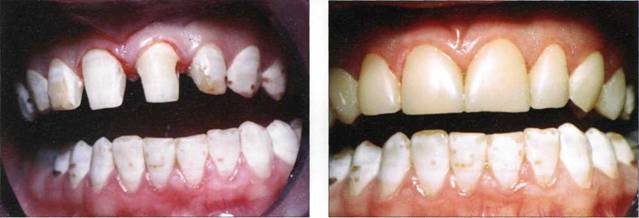

Клинический пример 22

Пациентке 35 лет. Диеколорит, тортоаномалии фронтальной группы зубов верхней челюсти. Произведена реконструкция верхних клыков, резцов материалом uEsthet-X" фирмы "DentSply".

Рис. 786. Исходная клиническая ситуация

Рис. 787. Конечный результат

Рис. 788. Конечный результат